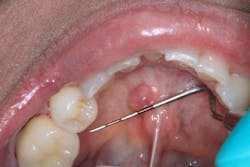

Patient: 74-year-old female

- 5 x 0.5-inch radiopaque mass on the left side, just anterior to the angle of the mandible

- Area is asymptomatic upon palpation

- Lesion has been present for at least six years